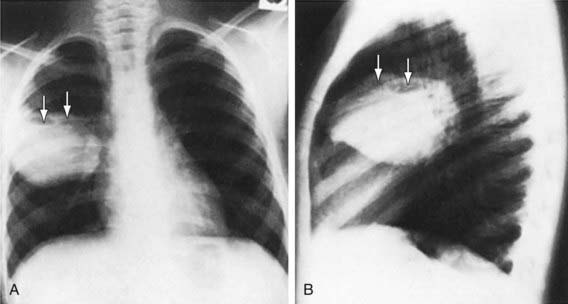

Diagnosis is most commonly made on the basis of chest radiography. Classically, the chest radiograph shows a parenchymal inflammation with a cavity containing an air-fluid level (Fig. 394-1). A chest CT scan can provide better anatomic definition of an abscess, including location and size (Fig. 394-2).

Figure 394-1 A and B, Multiloculated lung abscess (arrows).

(From Brook I: Lung abscess and pulmonary infections due to anaerobic bacteria. In Chernick V, Boat TF, Wilmott RW, et al, editors: Kendig’s disorders of the respiratory tract in children, ed 7, Philadelphia, 2006, Saunders, p 482.)